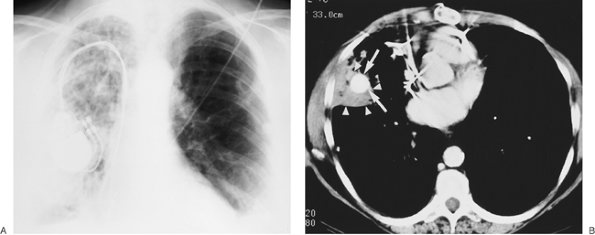

FIGURE 5-11. Pulmonary artery pseudoaneurysm as a complication of pulmonary artery catheter placement. A: AP recumbent chest radiograph in a 66-year-old woman with a history of chronic obstructive pulmonary disease and prior lung volume reduction surgery. The film was taken shortly after right heart catheterization, during which time a pulmonary artery catheter was placed into the right pulmonary artery to measure pulmonary capillary wedge pressure. The radiograph shows diffuse airspace disease in the right lung, consistent with acute pulmonary hemorrhage, which was new compared with a precatheterization radiograph. B: CT scan obtained after administration of intravenous contrast material, performed the same day as the chest radiograph in (A), shows an enhancing peripheral pulmonary artery pseudoaneurysm (arrows), with surrounding pulmonary hemorrhage (arrowheads). The pseudoaneurysm was embolized with coils by interventional radiologists, and the bleeding stopped.